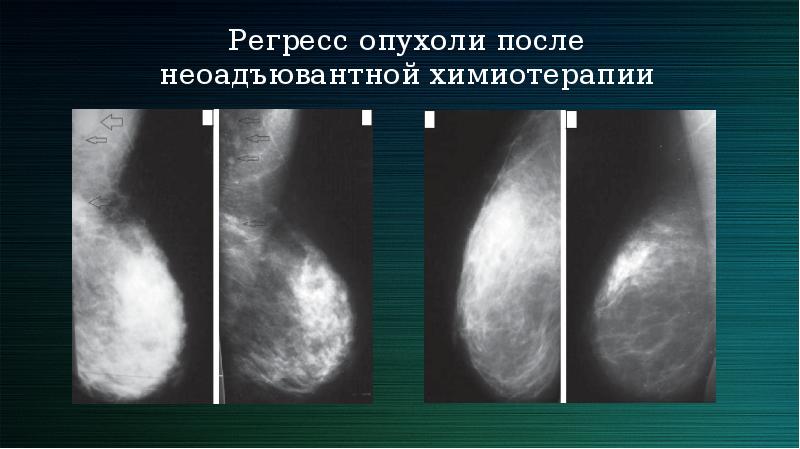

Таргетная терапия РМЖ: Инновации в лечении